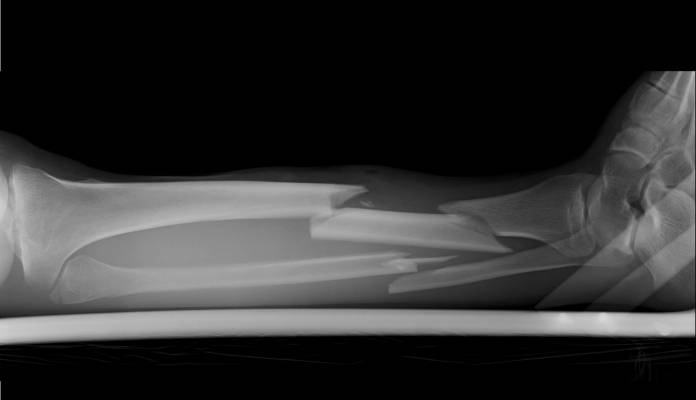

Der Schienbeinbruch (Tibiafraktur) ist einer der möglichen Knochenbrüche am Unterschenkel. Der Unterschenkel besteht aus zwei Knochen, dem Schienbein (Tibia) und dem annähernd parallel dazu laufenden Wadenbein (Fibula). Dabei ist das Schienbein in den meisten Bereichen dicker als das Wadenbein und trägt auch einen Großteil des Gewichtes. Ein Bruch des Schienbeins ist daher auch bedeutsamer als ein Bruch des Wadenbeins. Das Schienbein fällt als der Knochen am Unterschenkel auf, dessen Vorderrand unter der Haut tastbar ist. Es bildet mit seinem verdickten Anfang, dem Schienbeinkopf, einen Teil des Kniegelenks und mit dem Innenknöchel einen Teil des Sprunggelenks.

Unterschenkelbrüche entstehen allgemein meist durch Einwirkungen von Gewalt wie beispielsweise bei Verkehrsunfällen oder beim Sport. Schienbeinbrüche können verschiedene Formen annehmen, es kann sich um einen Schienbeinkopfbruch (Tibiakopffraktur), einen Schaftbruch (Tibiaschaftfraktur) oder einen Innenknöchelbruch (distale Tibiafraktur) handeln. Oftmals ist das Wadenbein ebenfalls gebrochen (Fibulafraktur).

Das Schienbein liegt direkt unter der Haut des Unterschenkels. Deshalb findet sich bei einer Fraktur des Schienbeins sehr oft ein offener Bruch, was bedeutet, dass die Bruchstück-Enden durch die Haut treten.